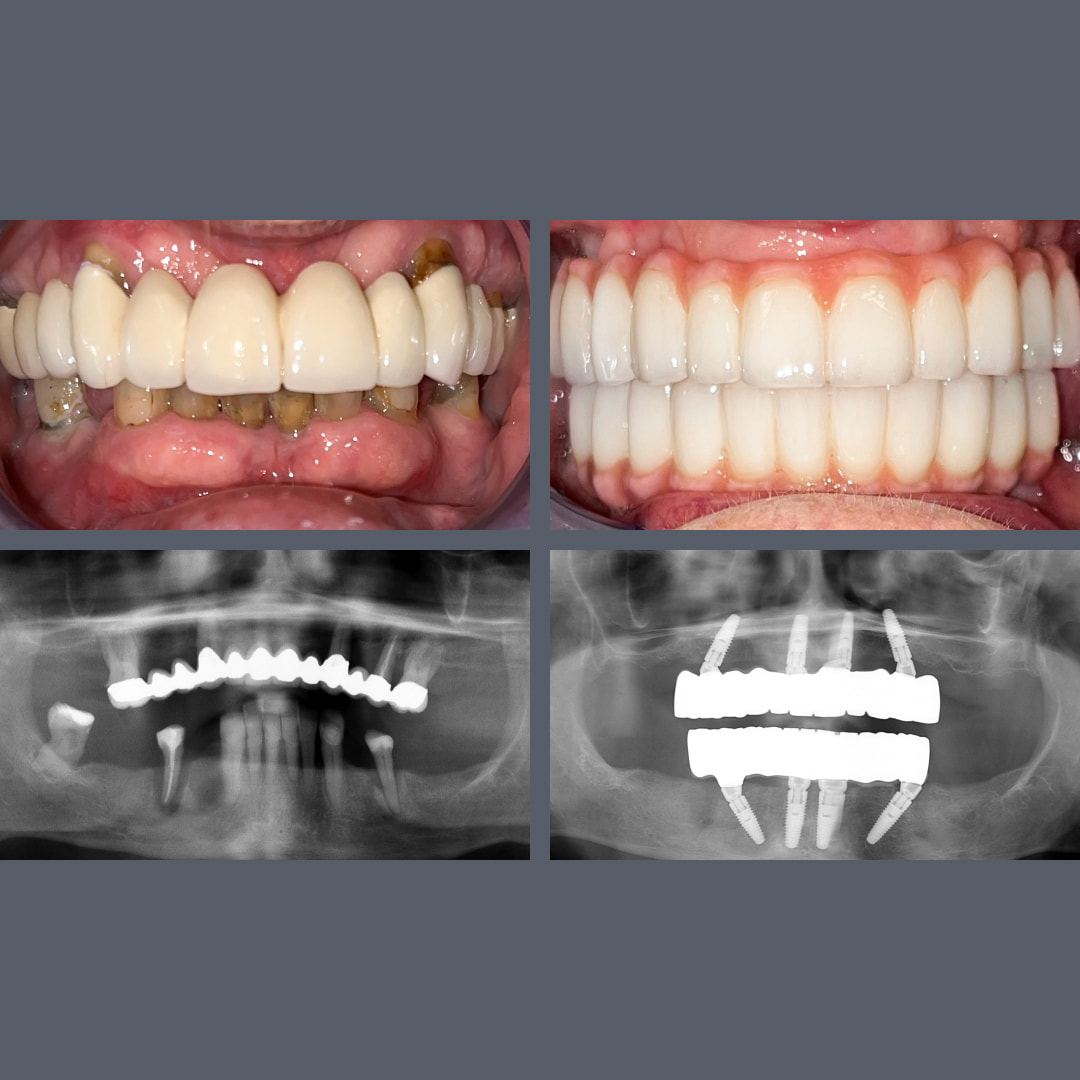

før og efter

Fra gammel bro til fast og æstetisk løsning: All-on-4® i overkæben på 5 måneder